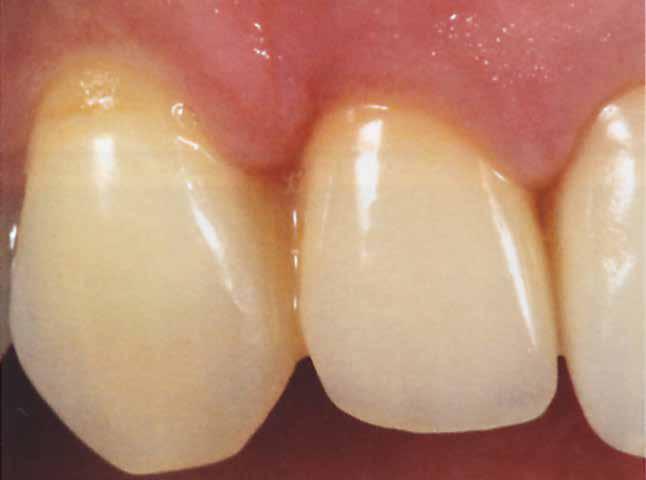

Végezetül részletfelvételek egy másik ragasztott hídról, amely hasonló módon készült, hat hónappal a behelyezés után (42–43. képek)

A hídtag enyhe mozgathatósága miatt az íny stimulálva volt. Ezzel a vérellátás további segítséget kapott, ami a lágyszövet kiváló adaptálódását hozta magával.